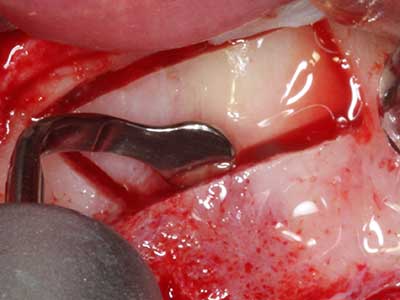

Si es preciso realizar intervenciones quirúrgicas en las que el hueso está en contacto directo con estructuras sensibles, como son los vasos sanguíneos o los nervios, los instrumentos rotativos presentan un enorme potencial de provocar lesiones iatrogénicas. Así, precisamente en la representación de nervios después de una lesión iatrogénica, o en el transcurso de la lateralización de un nervio para resecciones, reconstrucciones o incorporación de implantes, los equipos piezoeléctricos pueden resultar muy útiles para preparar la tapa ósea y retirar las partes de tejido duro cercanas al nervio (fig. 17-20). Por lo general, un ligero contacto del cordón nervioso con el inserto piezoeléctrico no tiene consecuencia alguna; ahora bien, un procedimiento poco cuidadoso con movimientos tipo sierra o piezas de trabajo sobre la base ósea aún existente puede provocar lesiones nerviosas temporales o incluso permanentes. Con todo, el riesgo de sufrir una lesión de este tipo se considera significativamente inferior que en los casos en los que se utilizan sierras y fresas (Pereira, Gealh et al. 2014).

Fig. 18: Preparación de una tapa cortical con la sierra ósea piezoeléctrica (Piezomed, W&H).

Fig. 19: Zona operada después de neurolisis y eliminación del osteomo.

Fig. 20: La tapa ósea extraída se readapta y se fija mediante un tornillo para osteosíntesis (KLS Martin, Tuttlingen).